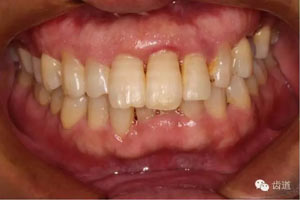

初診照片(正面照)

臨床檢查:11,21伸長(zhǎng)1-2mm,松動(dòng)1度,叩(+),21齦緣稍紅腫,唇側(cè)牙槽骨較豐滿,前牙咬合早接觸,中低位笑線,口腔衛(wèi)生一般。